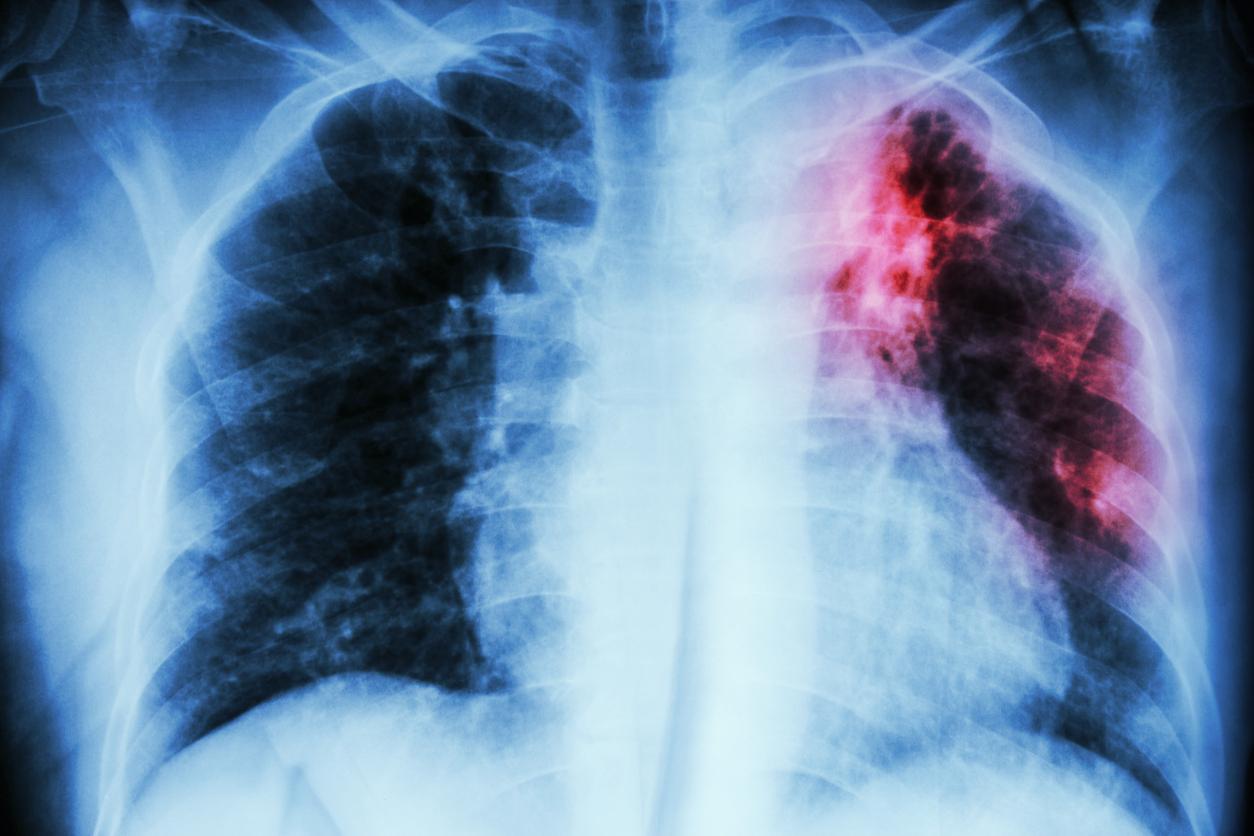

L’Organisation mondiale de la Santé (OMS) tire la sonnette d’alarme. La tuberculose, maladie infectieuse qui affecte le plus souvent les poumons, a présenté une nouvelle hausse des cas en 2023. Environ 8,2 millions de nouveaux cas de tuberculose ont été comptabilisés, selon son dernier rapport. Il s’agit ainsi du nombre le plus élevé enregistré depuis que l’organisme a commencé à suivre l’évolution de la maladie en 1995.

Ainsi, au total, l’agence estime qu’approximativement 10,8 millions de personnes vivaient avec l’infection respiratoire. En revanche, un signe encourageant a été repéré : le nombre de décès liés à la tuberculose a diminué de 1,32 million en 2022 à 1,25 million en 2023.